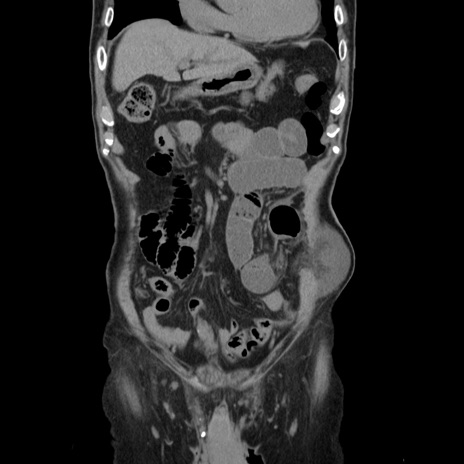

症例24(冠状断像)

【症例】80歳代男性

【主訴】左側腹部痛、嘔吐

【現病歴】本日早朝より左腹部に痛みあり。昼頃嘔吐認めたため、救急要請。

【既往歴】直腸癌(Mile手術)、胆摘

【身体所見】意識清明、BT 35.9℃、BP 221/93mmHg、SpO2 97%(RA) 、腹部:左ストーマ周囲に限局性の腹部膨隆あり。 膨隆部自発痛・圧痛あり・軟。

【データ】WBC 7700、CRP 0.09